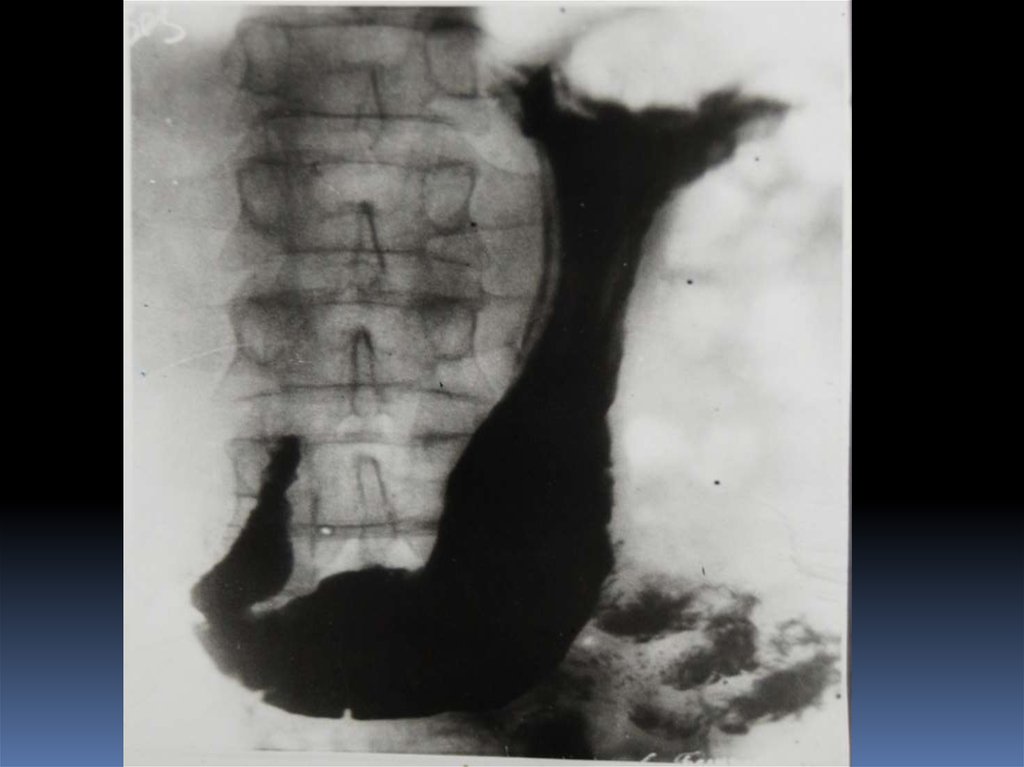

16. Рентгенодиагностика рака желудочно-кишечного тракта

Рентгенодиагностика

рака желудочнокишечного тракта